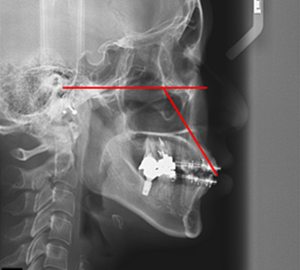

치료계획 수립 시 얼굴과학에 근거하여 입술위치를 평가한 후 앞니의 이상적인 각도와 위치를 설정합니다.

이를 바탕으로 발치할 치아, 치아이동량, 힘의 방향을 결정하고 치료합니다.

따라서 치료 도중 임상검사, 사진촬영, 엑스레이 촬영 등을 통해 입술 위치, 앞니 각도에 대한 지속적인 평가가 필요합니다.